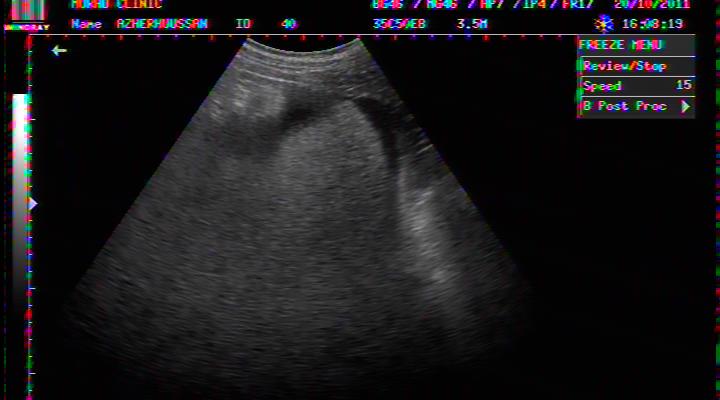

PELVIC ASCITES IN DHF